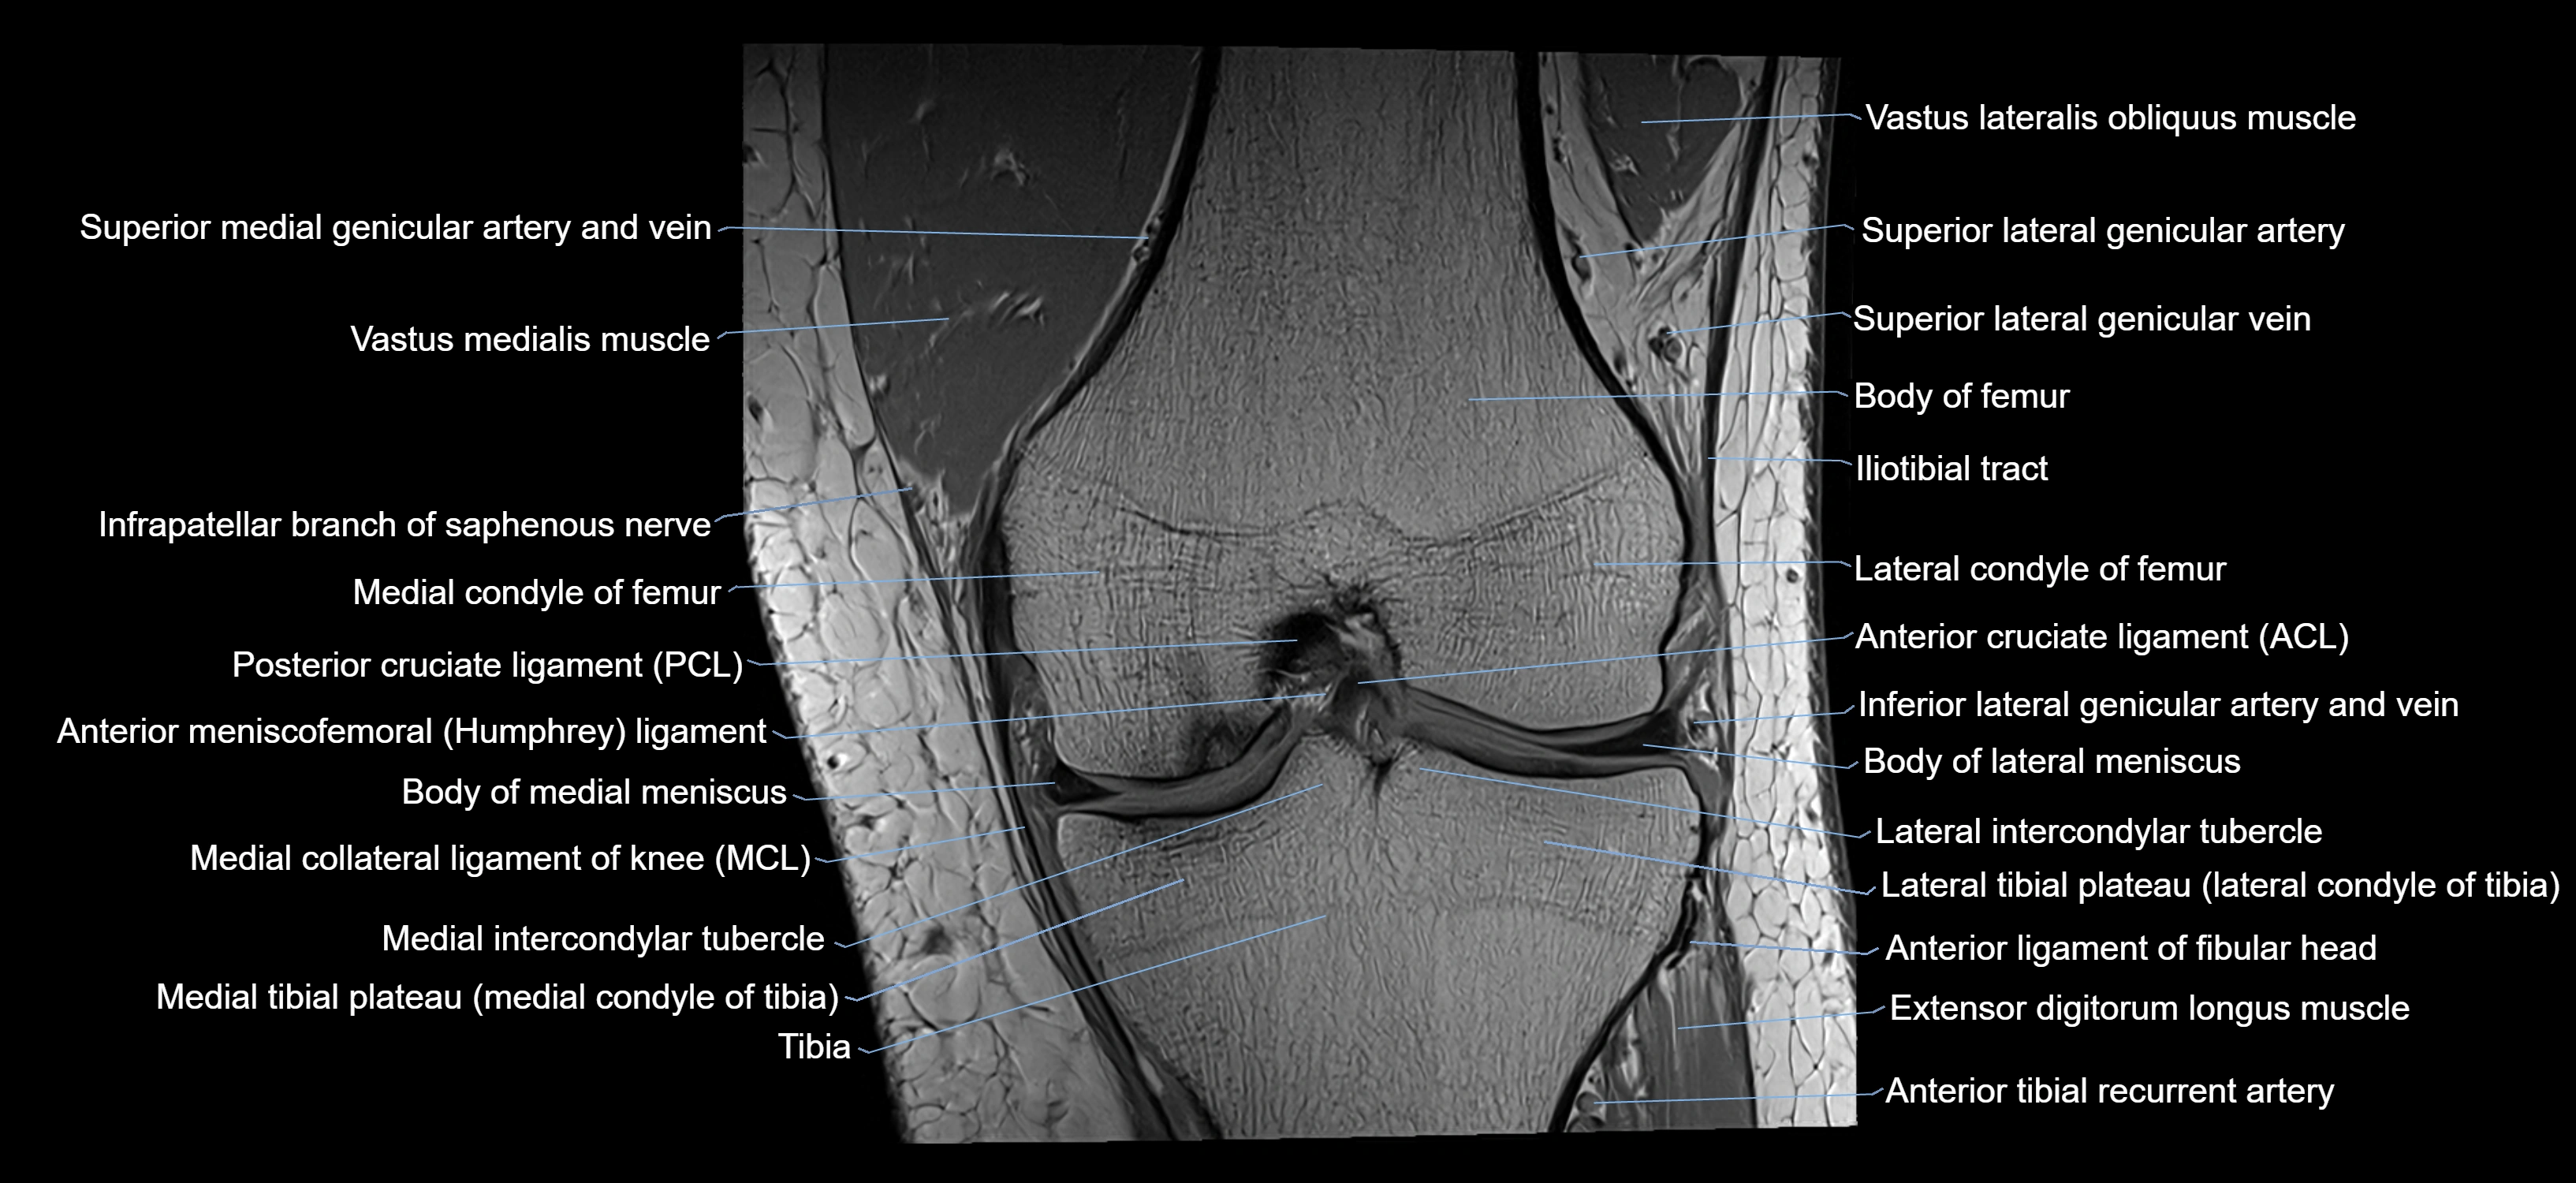

- Knee Joint

- Anterior cruciate ligament

- Anterior ligament of fibular head

- Anterior meniscofemoral ligament

- Body of lateral meniscus

- Body of medial meniscus

- Inferior lateral genicular artery

- Inferior lateral genicular vein

- Lateral condyle of femur

- Lateral condyle of tibia

- Lateral intercondylar tubercle

- Lateral tibial plateau

- Medial collateral ligament

- Medial condyle of femur

- Medial intercondylar tubercle

- Medial tibial plateau

- Posterior cruciate ligament

- Superior lateral genicular artery

- Superior lateral genicular vein

- Tibia

- Vastus Lateralis Obliquus Muscle

- Vastus medialis muscle